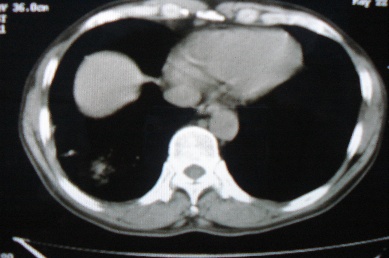

ct10716,男,59岁。发热咳嗽一天,咯血一次入院。

病灶中心有低密度,气体,病灶周围炎性浸润可能为肺脓肿,量体温、查个痰就是了,但肺脓肿一般都多少会有点兄水的。左肺下局部密度减低,小叶中心肺气肿。

右下肺病灶,边缘模糊,中心见低密度坏死区及气体影,结合病史较短,以发热为主,考虑右下肺脓肿,建议抗炎治疗后复查。